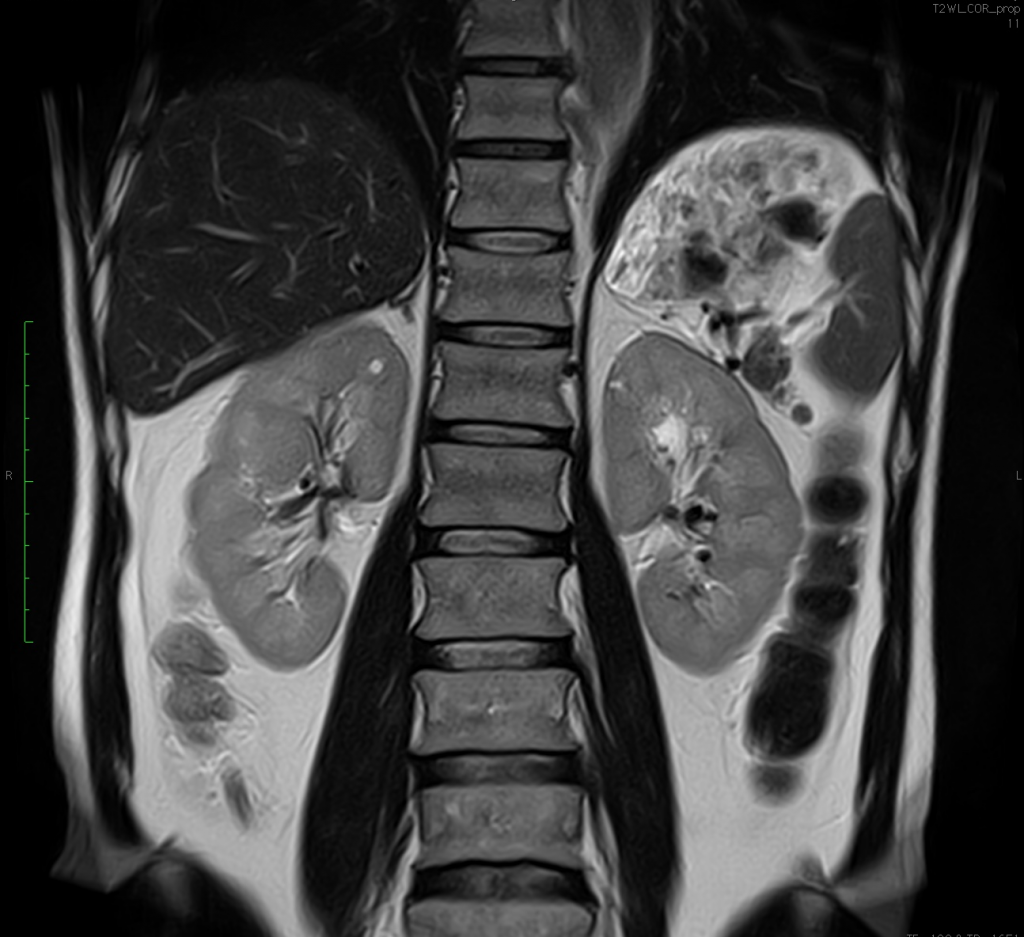

Integrated Coils with the top configuration in the industry.

- 24 Channels: Head&Neck, Abdomen, Pelvis

Clinical Images